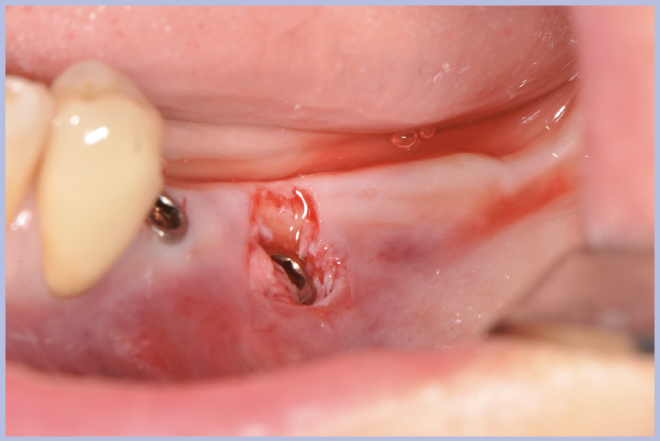

Dopo 3 mesi si esegue il rientro chirurgico con tecnica flapless per il posizionamento dei tappi di guarigione transmucosi, utilizzando la stessa mascherina chirurgica senza le boccole per guidare il percorso dei mucotomi (Figg. 31-36).

- Figg. 31-35 – Al momento della riapertura utilizzo della guida chirurgica per l’esposizione implantare

- Fig. 32

- Fig. 33

- Fig. 34

- Fig. 35

- Fig. 36 – Posizionamento dei tappi di guarigione